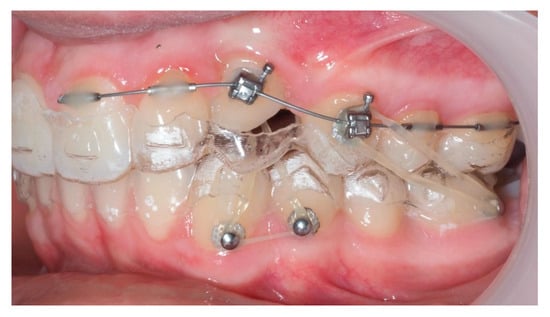

During vestibular traction, gingival removal was required. The canine presented mesial tipping and rotation. In the 14th month after the surgery, a bracket was bonded to tooth 23, following its inclination. A button was bonded on tooth 33 and connected by elastic to tooth 22 to stabilize the vertical position. Another elastic with a Class II vector was attached from the bracket on tooth 24 to a precision cut in the lower aligner (Figure 18).

Figure 18.

Vestibular traction of the canine, gingival removal, and elastic use for vertical stabilization; 14 months after the surgery.